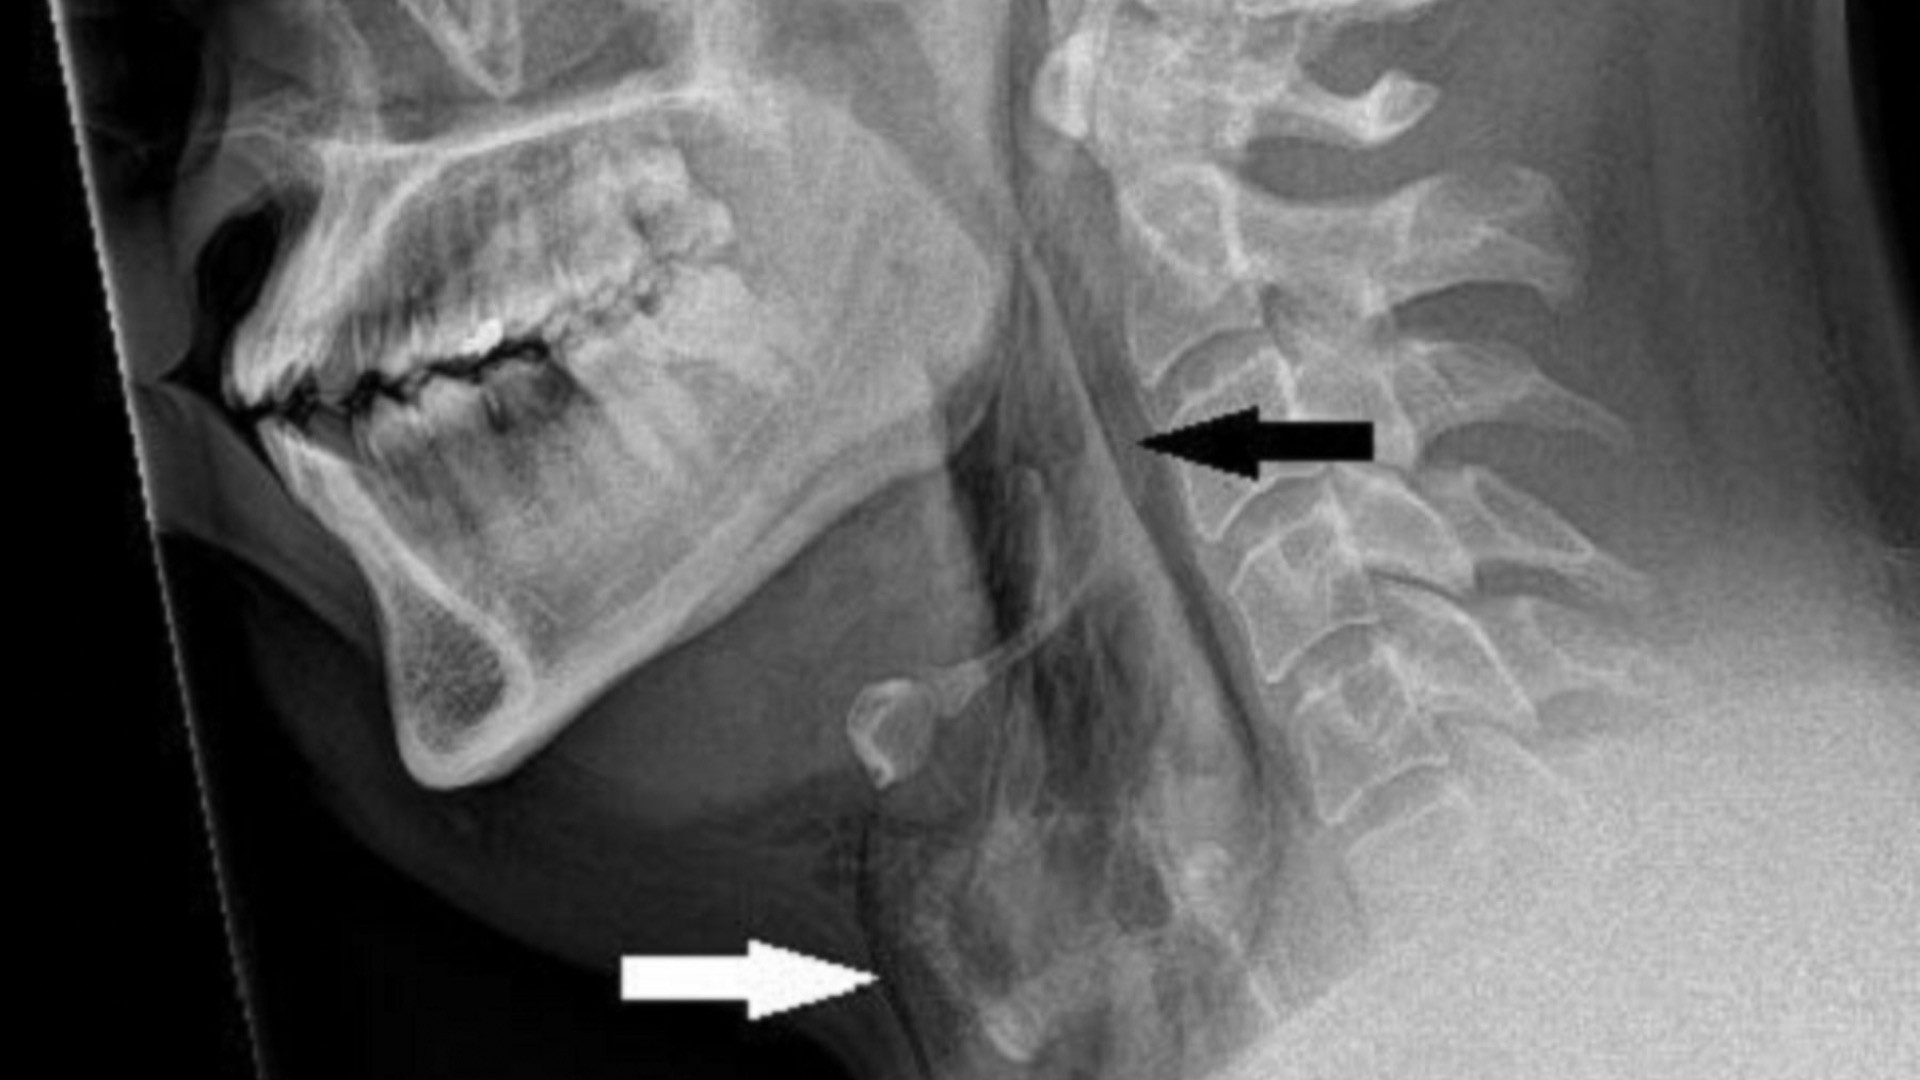

A 34-year-old man in Mexico suffered severe abdominal pain seconds after drinking a smoky cocktail infused with liquid nitrogen. He was found to have a ruptured stomach with pneumoperitoneum and underwent laparoscopic repair using tissue from his abdomen, recovering and being discharged three days later. The report highlights the dangers of consuming liquid nitrogen in beverages, which can rapidly expand as it warms, and notes that safety hinges on allowing the nitrogen to vaporize completely; the Leidenfrost effect may have helped shield tissue from cold burns.